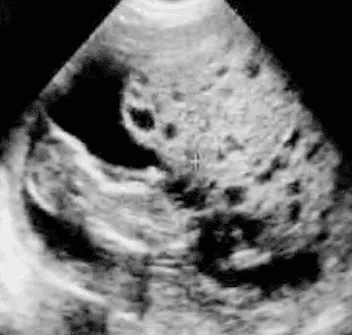

Phần tiêu đề “Cận lâm sàng”Siêu âm:

Hình ảnh “Siêu âm thai trứng bán phần”.

- Thai trứng bán phần: Hình ảnh nang nước không đồng nhất, có thể kèm túi thai hoặc phôi thoái hóa.